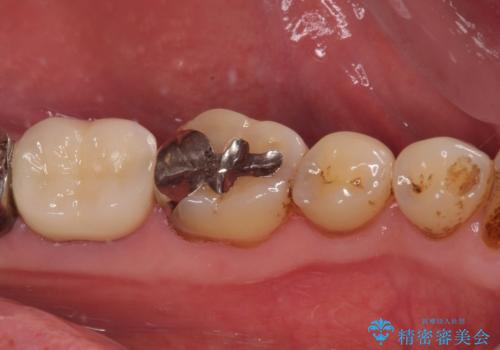

初回の根管治療後にはすぐに痛みが引き、食事の際に触れないように注意することがなくなったようです。

根管治療後6か月が経過してレントゲンを撮影したところ、非常に大きかった病変が小さくなっていることが確認されました。

今後も経過観察を継続していくこととなります。